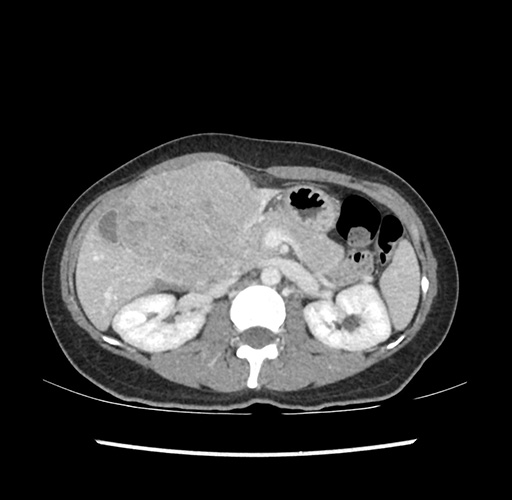

Imaging Analysis

Look through the patient's CT scan to identify any areas of concern for the necessary procedure.

Based on your CT findings, which issue(s) would give reason for "planned slowing down moment(s)" in this case?